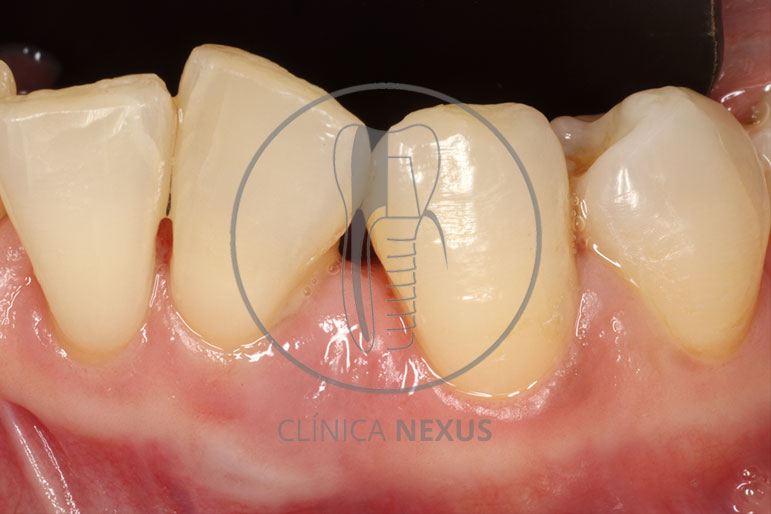

Tratamiento de defectos periodontales infraóseos en sector antero-inferior empleando gel de amelogeninas (Emdogain®) en combinación con un aloinjerto óseo (Biobank®). Paciente de 64 años, sin problemas médicos de relevancia, que presenta una periodontitis leve generalizada, pero asociada a presencia de defectos óseos verticales profundos a nivel de los espacios interdentales entre los caninos y los incisivos laterales inferiores. Tras la pertinente fase higiénica, se llevó a cabo una cirugía periodontal regenerativa, en la que, tras eliminar el cálculo subgingival (factor causal), se empleó una combinación de amelogeninas con un aloinjerto, para promover la regeneración tisular del periodonto perdido. Las imágenes clínicas y radiológicas, al año de seguimiento, reflejan un resultado terapéutico óptimo, con regeneración completa del tejido periodontal y mejora del pronóstico de los dientes involucrados.